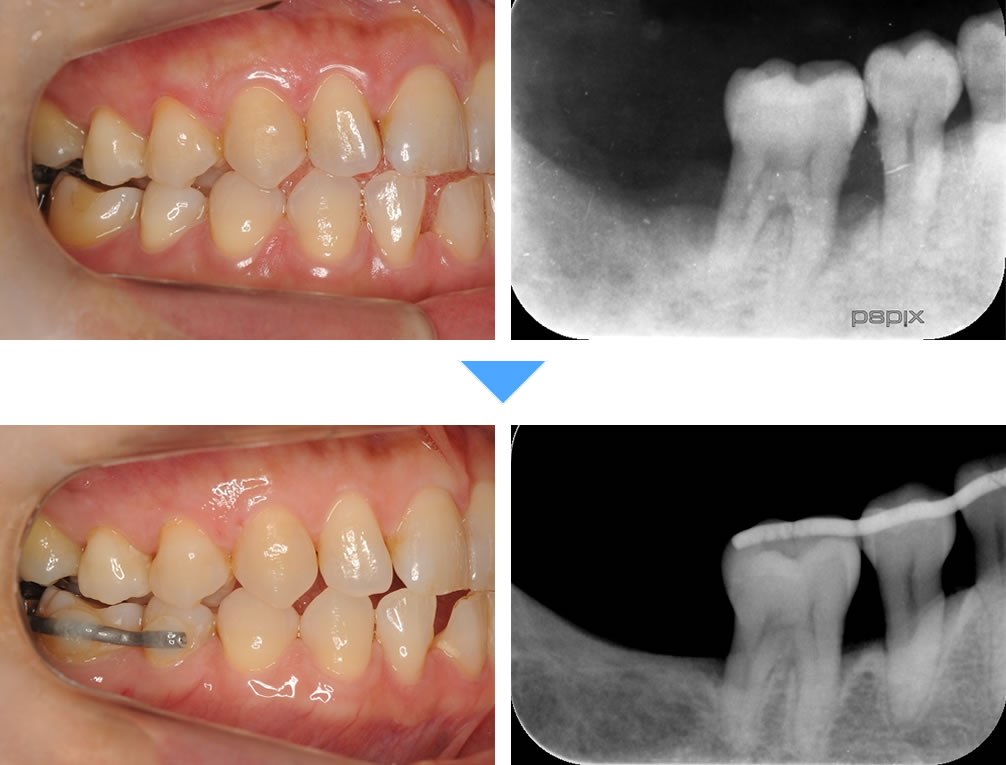

当院で実施した重度歯周病治療【MINST】の症例

| 治療期間 | 3ヵ月 |

|---|---|

| 治療回数 | 1回 |

| 治療費 | この歯1本あたり:1.65万円(税込) |

| この治療のリスク | ・術後しみることがあります |

初診時(上写真)、右下6番目の歯は今にも抜け落ちそうな状態でしたが、重度歯周病治療【MINST】によって、症状を改善し、術後1年後(下写真)には歯周組織もしっかりと再生しました。

※外科処置なし・再生材料も使用しておりません。